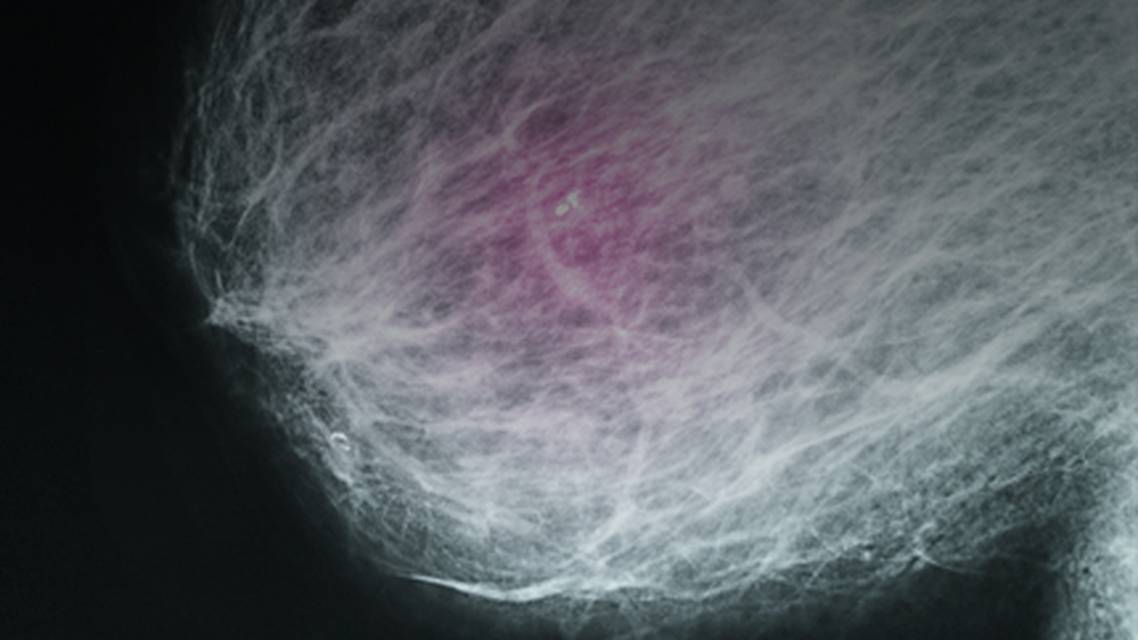

Breast Basics 101: What Every Woman Should Know About Breast Cancer Risk, Screening, & Detection